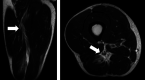

Methods: Two board-certified orthopaedic surgeons, highly experienced in reviewing MRIs, independently and retrospectively reviewed all MRIs collected at the Tokyo 2020 Olympic Games from clinical reports generated by board-certified musculoskeletal radiologists at the IOC Polyclinic. The presence and anatomical site of muscle injuries were classified as: type a: myofascial/peripheral; type b: muscle belly or musculotendinous junction; and type c: injury which extends into the tendon, with reference to the British Athletics Muscle Injury Classification.

Results: Fifty-nine MRI-detected muscle injuries were seen in 40 male and 19 female athletes. 24 athletes (41%) were unable to fully compete in their event. Fifty-two injuries (88%) involved lower extremity muscles with hamstring muscle injuries most common (32 of 59, 54%). Half of all muscle injuries occurred in athletes participating in athletics (30 of 59, 51%). 21 athletes (35%) sustained type a injuries, 14 athletes (24%) type b injuries and 24 athletes (41%) type c injuries. Of athletes with type c injuries, 18 (75%) did not complete their competition, a rate significantly higher than types a and b (OR 14.50, 95% CI 4.0 to 51.9, p<0.001).